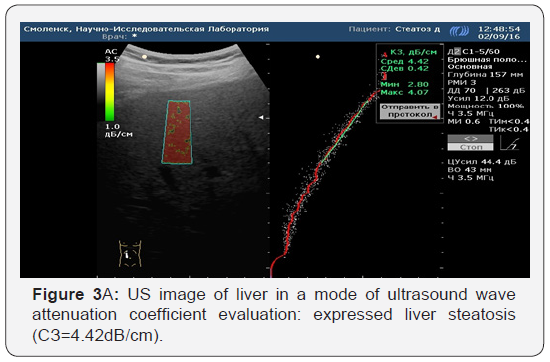

Various stages of NAFLD were identified in the histological study of liver biopsy materials. Evaluation of the results was carried out according to the SAF scale for semi-quantitative evaluation of gravity and the stage of NAFLD. We evaluated the correlation of the histological evaluation of liver biopsy samples with the ultrasound wave attenuation coefficient (Figure 2a, 2b & Figure 3a, 3b). All patients in the clinical group who underwent liver biopsy under the ultrasound were divided into groups, depending on the severity of fat changes in hepatocytes according to the SAF scale. Thus, by performing an analysis of the comparison of histological specimens of liver biopsy samples and ultrasound data of the quantitative evaluation of the ultrasound wave attenuation in dB/cm, it can be concluded that the correlation between liver biopsy and ultrasound wave attenuation coefficient evaluation is sufficient for in-formativeness at the initial and significant stages of liver steatosis (S0 r=0.86; S3 r=0.84). In stages S1 and S2, the informativity is lower, and it requires the introduction of more patients in the study protocols, carrying out liver elastography and increasing the number of liver biopsies in clinical groups.